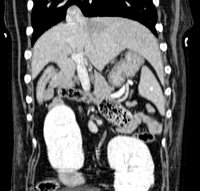

Abdomen & Pelvis

- Exploration of abdominal and pelvic masses

- Suspension of abdominal and pelvic foreign bodies

- Abdominal extension assessment in cancerology

- Exploration of portosystemic shunts by multiphase angioscan

- Exploration of abdominal organs: liver, spleen, pancreas, adrenals, kidneys, etc.

- Search for retroperitoneal foreign bodies

- Investigation of Cushing's syndromes

- Exploration of the urinary tree and search for ureteral ectopias